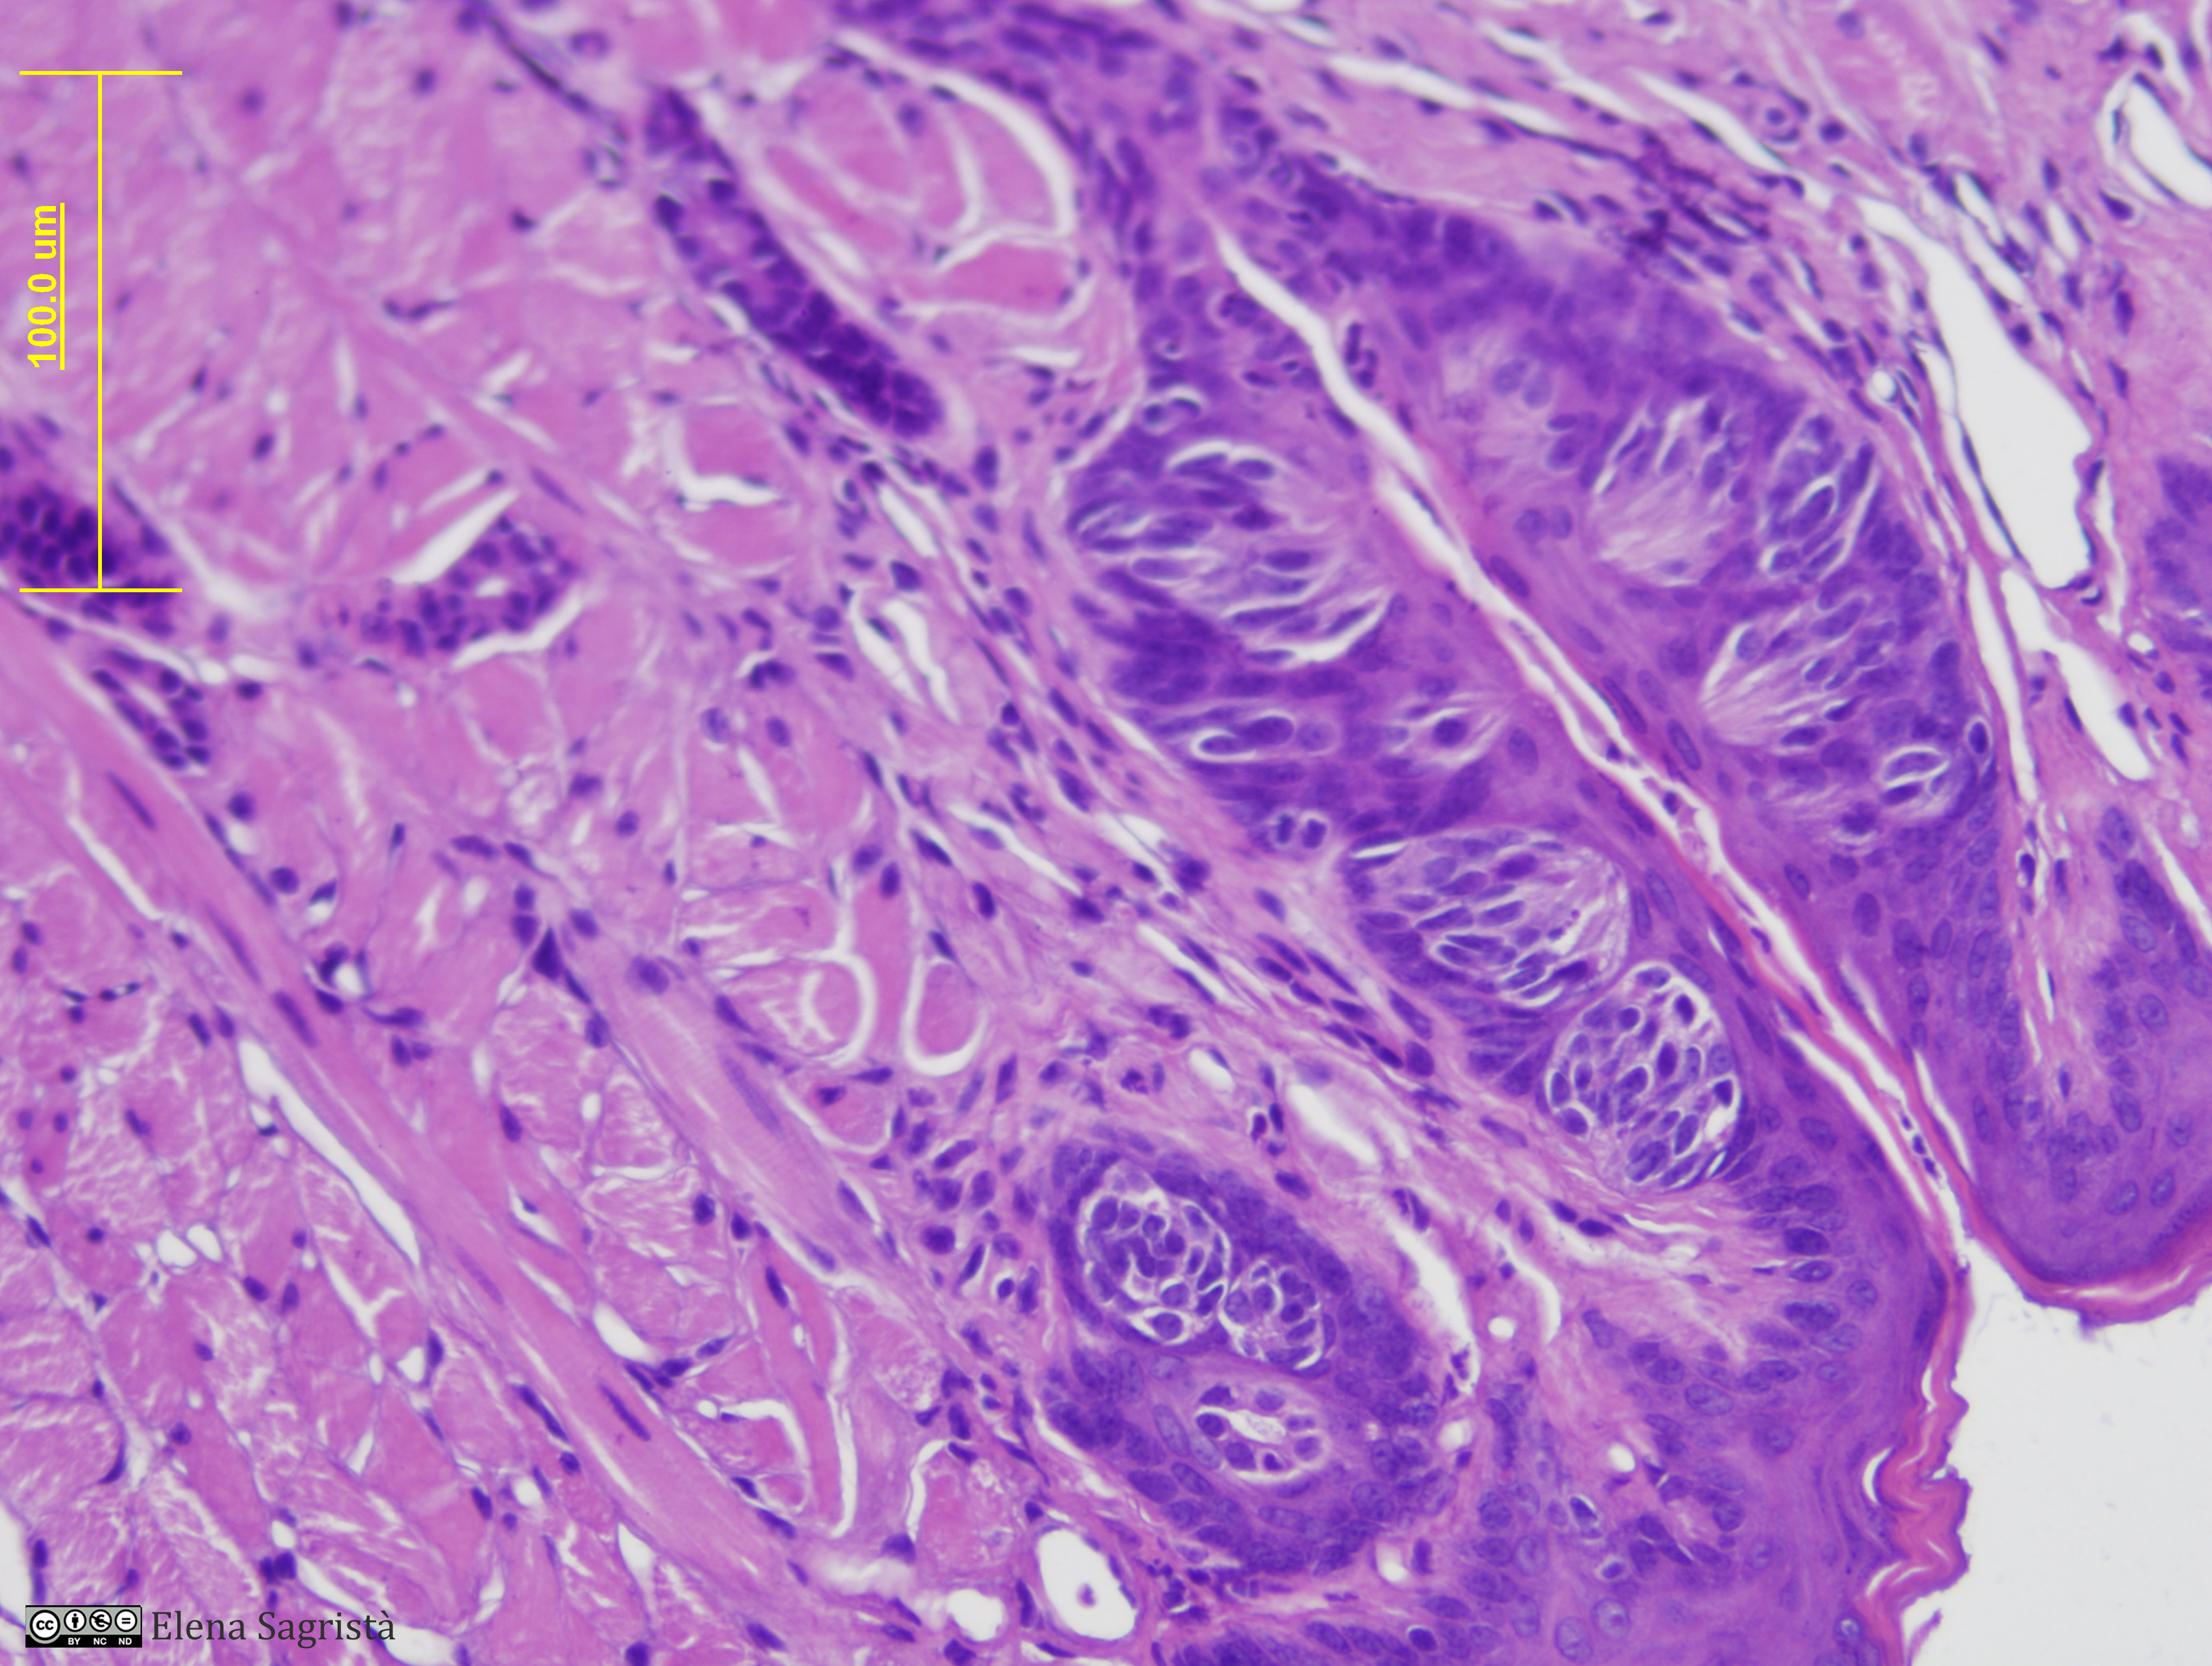

Histologia imatges: 14 Llengua

Imatges de preparacions histològiques de Llengua. Microscopia òptica.